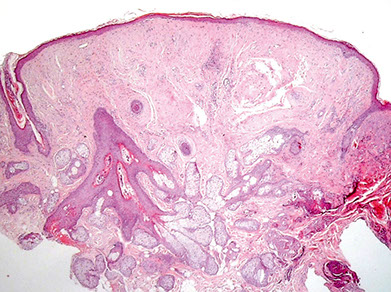

Cylindroma

- aka turban tumor

Kinda common b9 adnexal tumor of head/neck that appears as papules or nodules as a slow-growing and usually solitary tumor that is generally painless; etiology is unknown; F>>M

- may be assoc c AD Brooke-Spiegler syndrome if multiple in the dz's facial trichoepithelioma and eccrine poroma

Gross: looks like brain gyri

Gene: CYLD gene mutations cr 16q12-13

Micro: islands of basaloid cells in jigsaw pattern c scant cytoplasm surrounded by thick pink hyaline membrane and hyaline droplets bwt islands

- 2 types of epithelial cells peripheral cell (large basophilic nucleus which palisades); pilar cell (centrally located c vesicular chromatin pattern)

Tx: simple surgical excision can be curative

Px: excellent

- rarely can transform to a malignant lesion